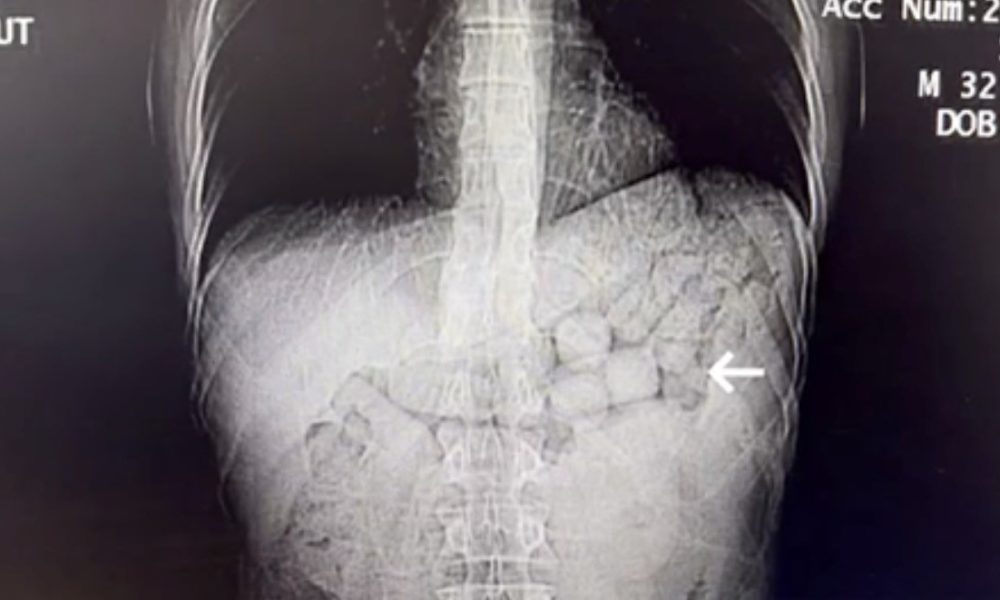

Akciğerlerdeki hava keseciklerinin geri dönüşü olmayan şekilde hasar görmesiyle ortaya çıkan ve hastalarda şiddetli nefes darlığına yol açan amfizem, hayat kalitesini ciddi biçimde düşüren önemli bir...